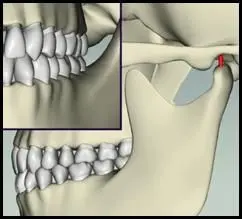

Occlusion analysis begins in the mouth and continues on models of the teeth mounted on measured articulators. Contact patterns and interferences are evaluated. Poor occlusion stresses the joints and unstable joints degrade the bite.

Part 1. Stabilize the joints with an orthopedic splint. Adjusted over time to remove interference from the teeth, balance the pressure on the joints and allow the joints to find a healthy, adapted home position and a functional movement track.

Part 2. Adjust the occlusion to match the stabilized jaw joints. This naturally protects both the joints and the teeth, which allows normal relaxation in the muscles. Muscles both stabilize and power the movement of the jaw.

In some cases, surgery is needed to restore jaw-based occlusion. Surgery requires that the TM joints are stable and well adapted.